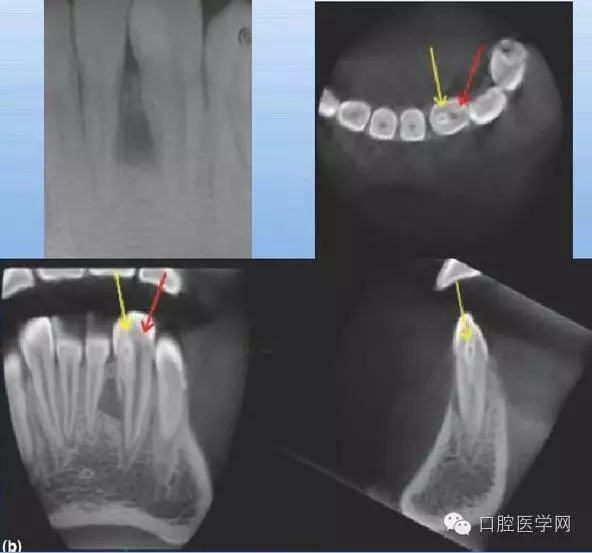

畸形中央尖

X線表現(xiàn):剛萌出的牙咬合面中央窩處,可見圓錐形突起的小牙尖;中央尖磨損或折斷,可見牙根短,根管粗大,常伴有根尖感染。

牙中牙

X線表現(xiàn):舌側(cè)窩陷入過深,形似一小牙包于牙髓中。